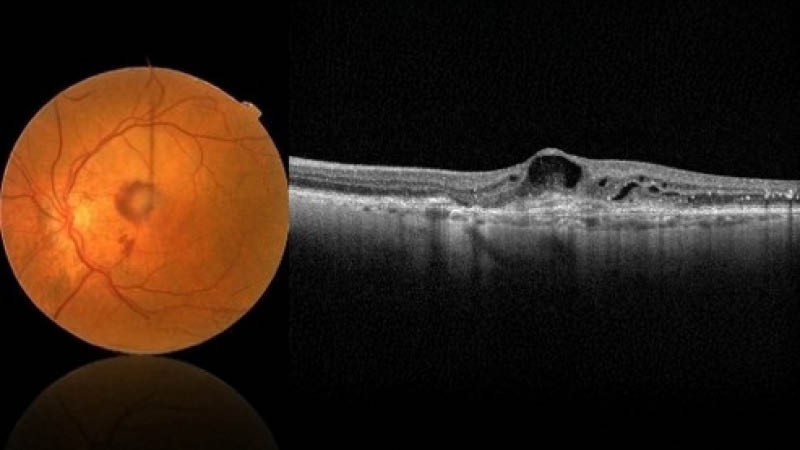

2. Feuchte AMD (neovaskuläre / exsudative AMD)

- Rascher Verlauf

- Flüssigkeitsansammlungen (intraretinal oder subretinal)

- Choroidale Neovaskularisation (CNV) durch Einwachsen pathologischer Gefäße aus der Aderhaut

- Blutungen möglich

- Endstadium: zentrale Narbenbildung (Junius-Kuhnt-Makulopathie)

- Optische Kohärenztomographie (OCT)